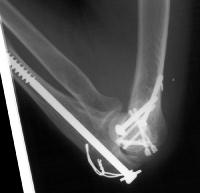

Clinical Example: Transcondylar distal humerus fracture repaired with Herbert screws

Transcondylar distal humerus fractures are usually high energy comminuted difficult fractures, technically difficult to manage. Anatomic reduction, rigid fixation and early motion are desirable, if technically possible. There are a variety of techniques for fixation. Here, Herbert screws were used to secure the two central purely osteochondral fracture fragments to each other and to the proximal humerus.

The olecranon osteotomy was closed with a 6.5 mm lag screw and (belt and suspenders) tension band technique.

Click for larger image

Anatomic reduction.